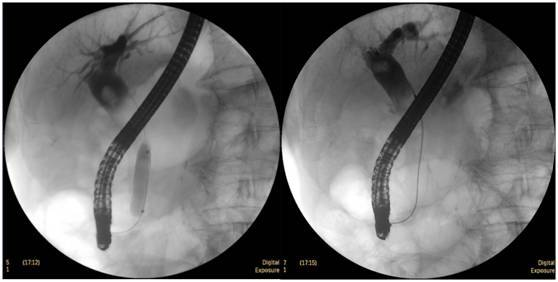

膽總管結(jié)石

柱狀球囊擴張完全,膽總管擴張,下段見充盈缺損影。

膽總管擴張,下段見明顯充盈缺損(上圖為反片且局部放大后效果)

柱狀球囊擴張膽總管下段及乳頭(上圖為使用取石網(wǎng)籃取石)。